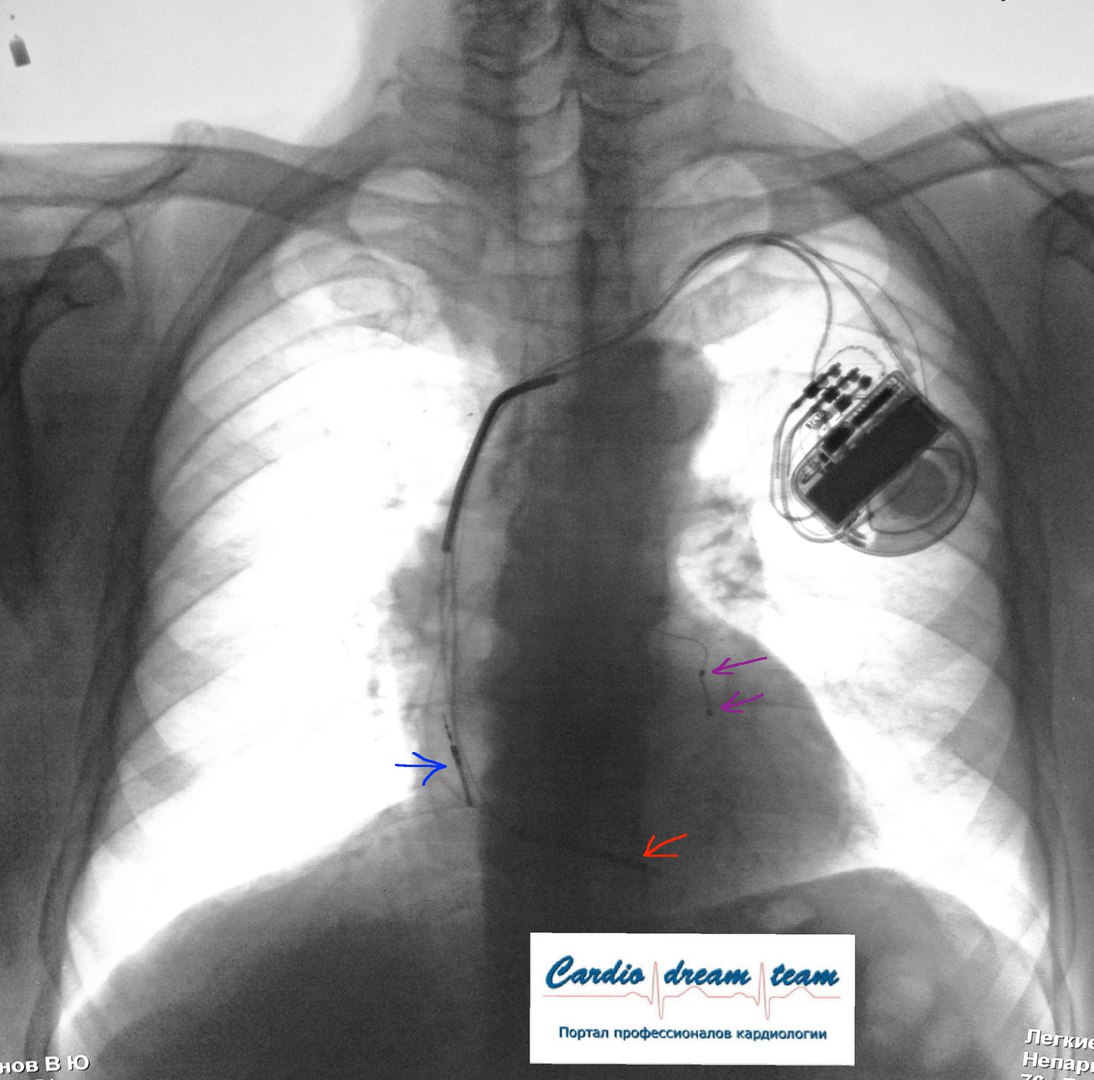

ИКД + RCT на рентгене. Синий - предсердный электрод. Сиреневые желудочковые для синхронизации. Красный электрод для дефибрилляции. Всё на месте.